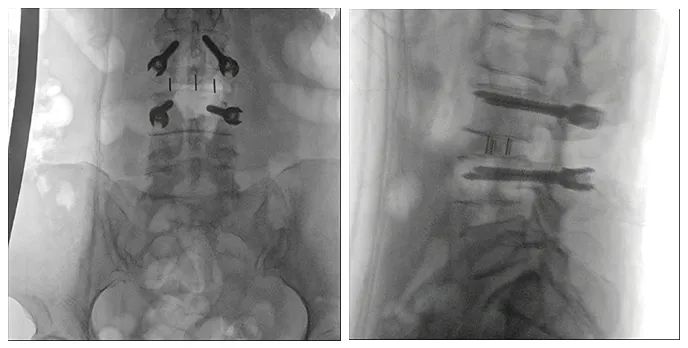

病例二

患者:女性,58歲

術(shù)式:腰骶椎椎體間融合術(shù)

患者一個(gè)月前因雙側(cè)下肢疼痛至醫(yī)院就診,診斷為腰椎間盤突出。患者自行至診所就診,予以推拿牽引術(shù),疼痛未明顯緩解,到醫(yī)院進(jìn)一步治療。影像診斷:L3-4椎間盤突出,椎管變窄(中央型)。

術(shù)前影像

使用普愛醫(yī)療術(shù)中三維導(dǎo)航C臂進(jìn)行透視,根據(jù)透視影像引導(dǎo)確認(rèn)責(zé)任間盤、規(guī)劃手術(shù)方案,充分暴露骨組織,并通過(guò)專業(yè)器械切除椎板,暴露神經(jīng)及椎管;在C形臂的引導(dǎo)下,確定責(zé)任間盤上下椎體椎弓根位置,制定進(jìn)針點(diǎn)及進(jìn)針?lè)较颍刈倒较蛑踩爰怪葆斶M(jìn)行固定;放入椎間融合器,加固螺釘。最后再進(jìn)行C形臂透視,確認(rèn)手術(shù)的完成效果。

手術(shù)效果確認(rèn)